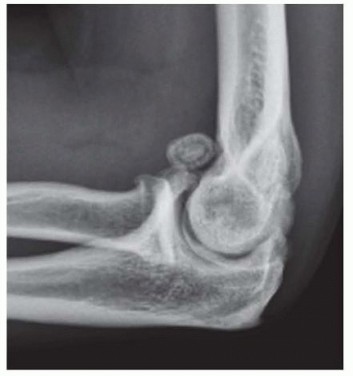

15 MIN READ Surgical Management of Traumatic Conditions of the Elbow: Interposition Arthroplasty يناير 2023 Read More